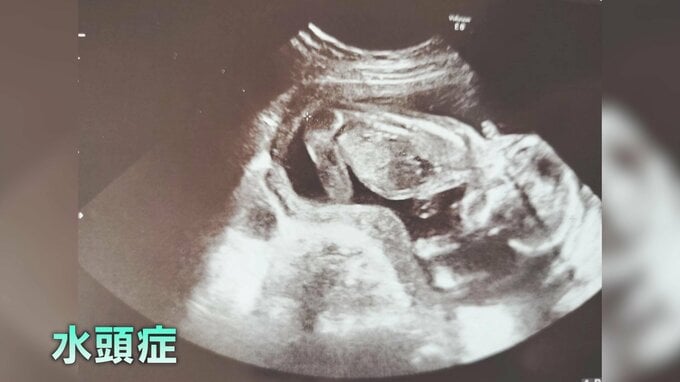

蒼くんには、生まれる前から「X連鎖性遺伝性水頭症」という病気があります。X染色体上の遺伝子の変異によって引き起こされる先天性の病気で、頭の中に水が溜まって脳が圧迫され、知能や身体の発達スピードに遅れが出るとされています。

「妊娠20週目くらいの時に、蒼の脳内の『脳室』が水でどんどん拡大されて、エコー画像で見ると脳内が水で真っ黒になってしまっているのが少しずつ明らかになってきて…。『どうしたら、この子の命が健康だったんだろう…』そんなことを思っていました」